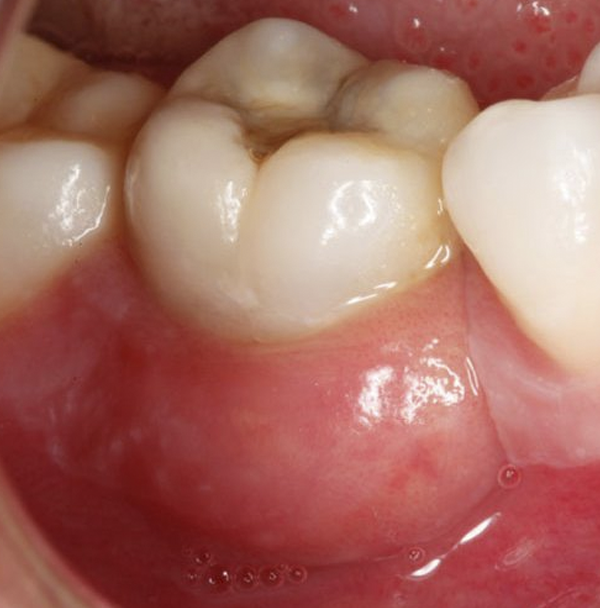

Gingivitis

Es la enfermedad de las encías más frecuentes, caracterizada principalmente por:

• Encías sensibles y sangrantes con facilidad

• Evidente inflamación

• Halitosis (mal aliento).

• Notorio acumulo de placa bacteriana, con coloraciones marrones y negras.

Cuando no es atendida, llega a complicarse, poniéndote en riesgo incluso de perder tus dientes.